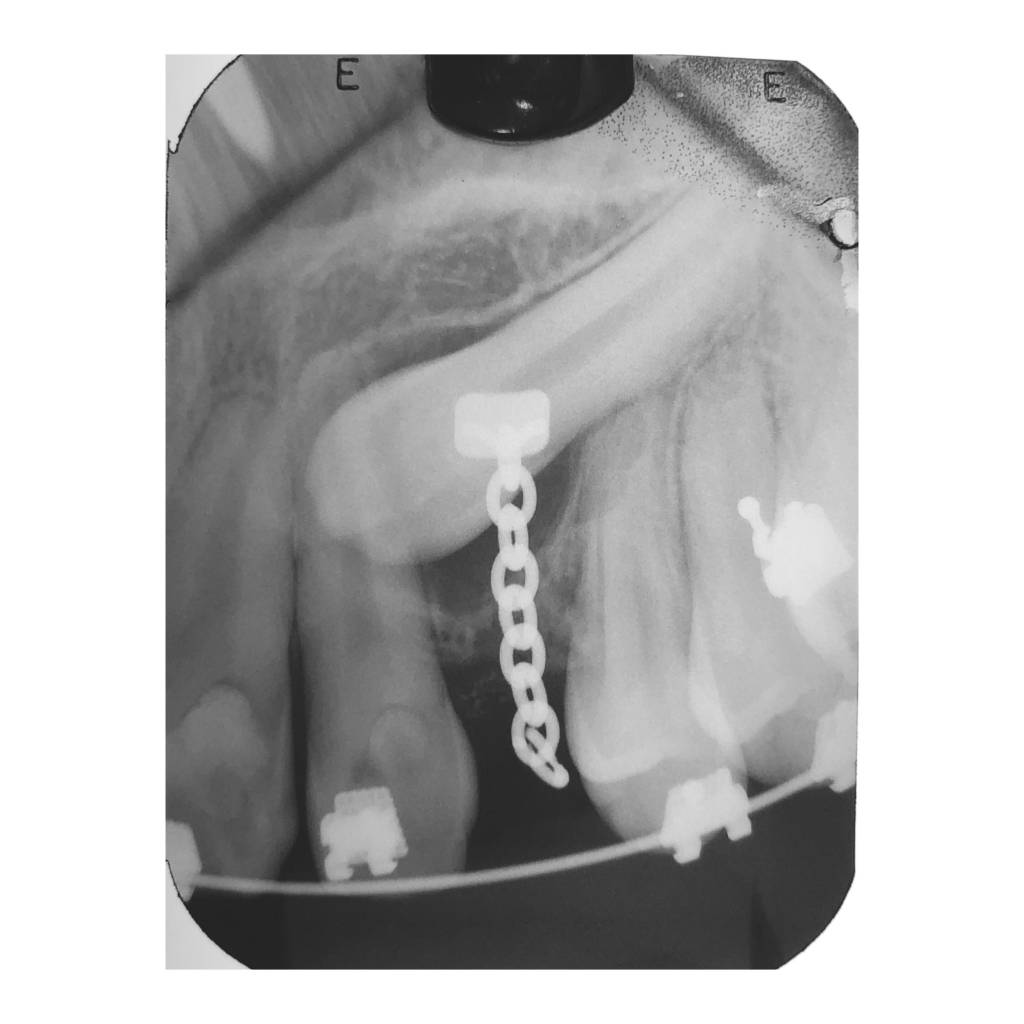

Cada cirugía comienza con un diagnóstico detallado mediante estudios radiográficos y, cuando es necesario, tomografías digitales que nos permiten planificar el procedimiento con exactitud. Esto no solo optimiza los resultados, sino que también reduce la posibilidad de complicaciones y mejora el postoperatorio.